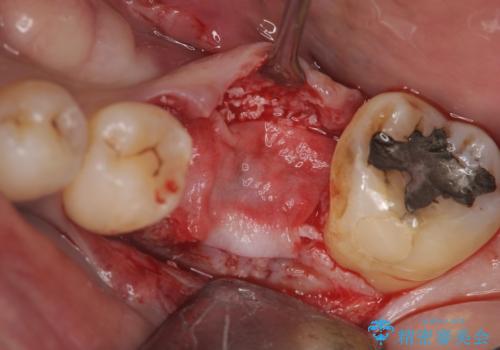

失った奥歯をインプラントで機能回復

- 失った歯の機能回復を希望され来院されました。

取り外しの必要な入れ歯、隣の歯を削る必要のあるブリッジに心理的抵抗があり、インプラントを用いて咬合機能を回復していくこととなりました。

元あった歯のようにしっかりと咬合機能が回復することができました。